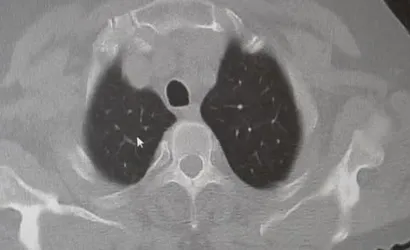

Karakurt, KOAH'ı zararlı maddelerin akciğeri tahrip etmesiyle ortaya çıkan bir hastalık olarak tanımladı. Buna ilişkin değerlendirmesinde, "KOAH önlenebilir bir rahatsızlıktır; sigaranın bırakılmasıyla birlikte tamamen ortadan kalkacaktır" ifadesini kullandı. Ayrıca hava kirliliği, iş yerlerinde kimyasal maddelere maruz kalma ve enfeksiyonların da KOAH nedenleri arasında yer aldığına vurgu yaptı.

Zatürre: Belirtiler, ayırıcı tanı ve riskler

Prof. Dr. Karakurt, KOAH'lı hastaların akciğer dokusu tahrip olduğunda enfeksiyonlara daha yatkın hale geldiğini ve enfeksiyonların daha güç geçebildiğini belirtti: "Akciğer dokusunun tahrip olduğu her durumda hastaların enfeksiyona karşı eğilimi artar ve enfeksiyona yakalandıklarında bunun geçmesi güç olur."

Zatürrenin belirtileri arasında öksürük ve balgam artışı, yüksek ateş (örneğin 38,5°C üzeri), artan nefes darlığı, titreme ve bilinç bozukluğu sayılabilir. Karakurt, bronşit ile zatürrenin ayırt edilmesinin önemli olduğunu; bronşitin daha çok bronşları, zatürrenin ise alveolleri (hava keseciklerini) etkilediğini vurguladı. Bronşitten ölüm nadirken, zatürrenin yaklaşık %10 civarında bir ölüm oranı ile seyrettiğini ve bu oranın yaşla birlikte arttığını kaydetti.